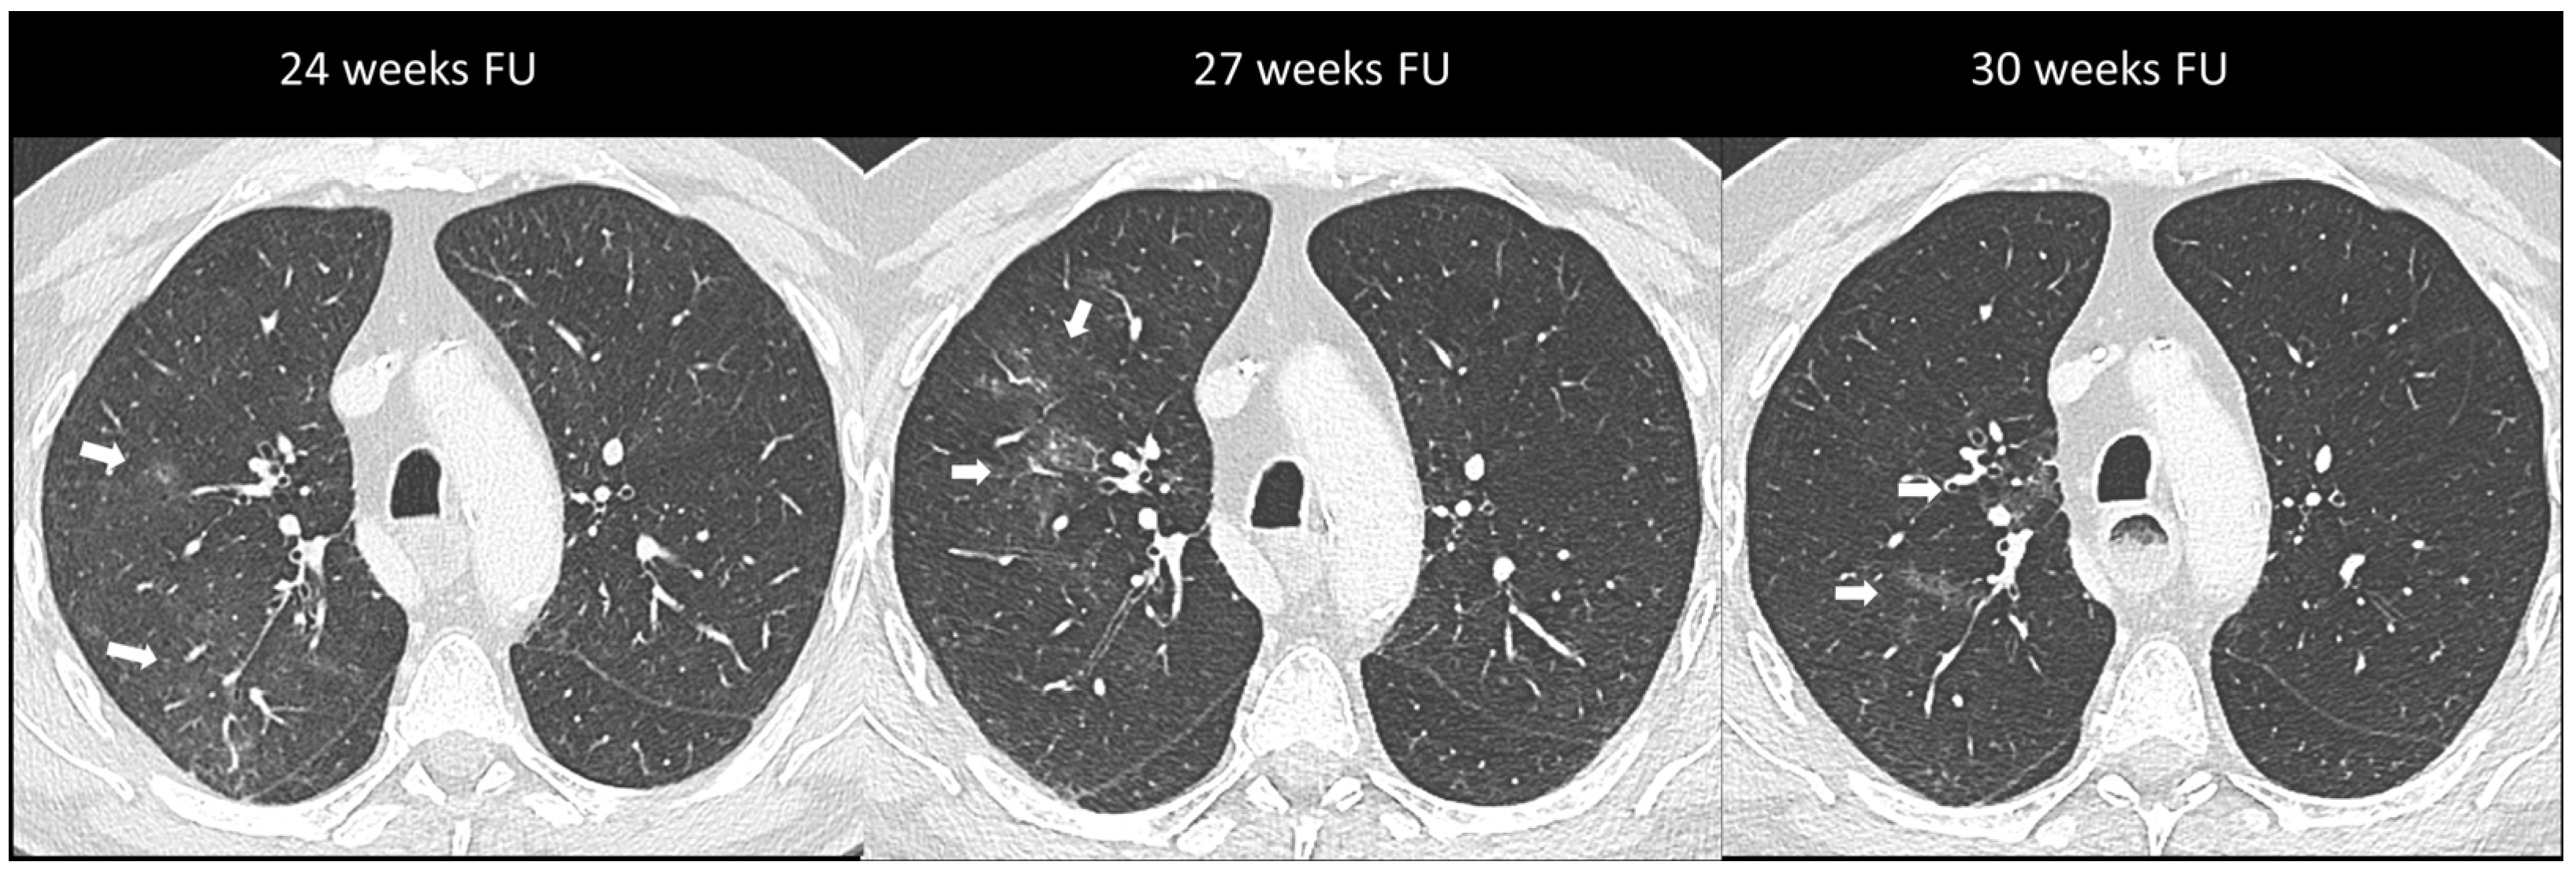

Figure 3.

Immuno-related pneumonitis with simple pulmonary eosinophilia pattern pathologically confirmed in a patient with metastatic esophageal cancer receiving chemotherapy and antiPD-1 treatment. The follow-up scans show multiple “migratory” patchy ground-glass opacities in the upper right lobe (arrow).

Imaging plays a major role in the identification, characterization, and follow-up of pulmonary irAEs. Chest X-ray is not recommended due to its limited sensitivity and specificity in detecting ICI pulmonary abnormalities [23]. Chest CT is the preferred imaging modality for suspected ir-pneumonitis with common radiological patterns including organizing pneumonia (OP), simple pulmonary eosinophilia (SPE), hypersensitivity pneumonitis (HP), nonspecific interstitial pneumonia (NSIP), and acute interstitial pneumonitis/diffuse alveolar damage (AIP/DAD) [23,25,39]. Organizing pneumonia is the most frequent pattern and it is generally marked by peribronchovascular or subpleural consolidations or patchy ground-glass opacities, which often migrate over subsequent scans (Figure 2). Interestingly, the “halo sign”, a typical OP feature characterized by ground-glass opacity with a peripheral rim of consolidation, is uncommon in ir-pneumonitis. The extent of the lung involvement correlates with the severity of pneumonitis. A simple pulmonary eosinophilia pattern is usually detected in asymptomatic patients and presents as transient and migratory ground-glass opacities or nodules that may regress spontaneously (Figure 3). Nonspecific interstitial pneumonia typically shows bilateral and symmetrical peripheral ground-glass opacities with lower lobe predominance, which may be associated with reticulations and traction bronchiectasis, while hypersensitivity pneumonitis manifests as centrilobular nodules and lobular hypoattenuations representing small-airway disease. Acute interstitial pneumonitis/diffuse alveolar damage pattern is generally reported in most severe cases and it is characterized by extensive bilateral ground-glass opacities and dependent alveolar consolidations with bronchiectasis appearing in subsequent scans. Micronodules in three-in-bud distribution resembling infectious bronchiolitis as well as a single nodular or mass-like appearance mimicking malignancy have also been described [23,39,40]. Contrast injection is not required; however, it might be performed in routine cancer restaging or in suspected complications such as pulmonary embolism.